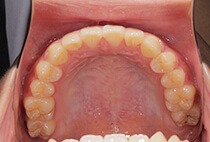

治療前

治療後

しっかり前歯を下げるために、インプラントアンカーを使用してコントロールしました。

かみ合わせが整うと咬筋の過緊張が改善。

過緊張による筋肉肥大も改善しフェイスラインもすっきりしました。